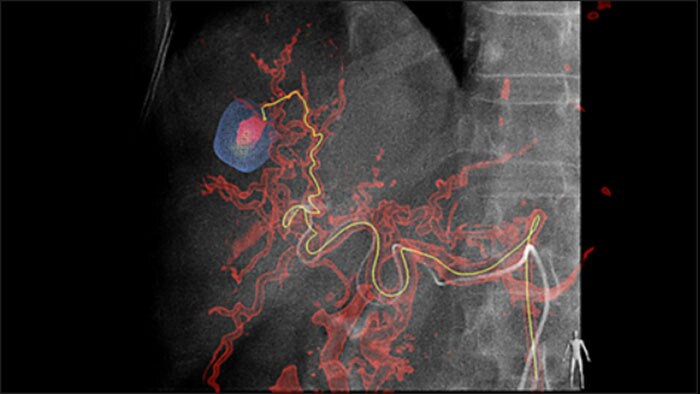

A Detecção Automática de Alimentação pode aprimorar de forma significativa a detecção da artéria alimentadora. O recurso EmboGuide facilita a maximização da eficácia de seus procedimentos de TACE devido ao seu potencial de aumento da sensibilidade, redução de falsos positivos e maximização do acordo interleitores.1 O EmboGuide também fornece uma eficiente orientação 3D ao vivo baseada no fluxo de trabalho com detecção automática de alimentação.1

A adoção de técnicas de quimioterapia/radioembolização como TACE e SIRT impulsionam a necessidade de padronização e eficiência. Caso após caso, você precisa localizar os tumores, identificar todos os vasos alimentadores e planejar/executar a abordagem intervencionista apropriada de forma confiável e consistente. Nossa solução de Detecção Automática de Alimentação pode aprimorar de forma significativa a detecção da artéria alimentadora em comparação com o uso isolado da Tomografia Computadorizada de Feixe Cônico. O recurso EmboGuide facilita a maximização da eficácia de seus procedimentos de TACE devido ao seu potencial de aumento da sensibilidade, redução de falsos positivos e maximização do acordo interleitores.1

A capacidade de detectar e diferenciar nódulos hepáticos e identificar vasos alimentadores muito pequenos é fundamental para determinar a terapia adequada. Navegar para a região de interesse alcançando todos os alimentadores e, ao mesmo tempo, manter-se seletivo quanto à lesão aumenta as chances de sucesso. A confirmação do desfecho do tratamento e do sucesso do tratamento enquanto o paciente ainda está na mesa aumenta a confiança no desfecho clínico.